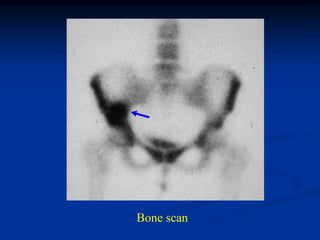

Bone scan

Axial T-2 MRI